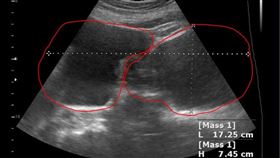

8旬嬤腹脹以為發福 檢查驚見大水瘤

女性肚子變大別以為是單純的發福,也有可能是婦科腫瘤。...